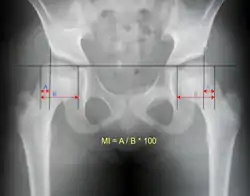

Anterior dislocation of the hip Reimer's migration index can be used to indicate hip dislocation. The migration index (MI) is normally less than 33%.[18]

Reimer's migration index can be used to indicate hip dislocation. The migration index (MI) is normally less than 33%.[18]